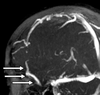

4

Q

A

falx cerebri